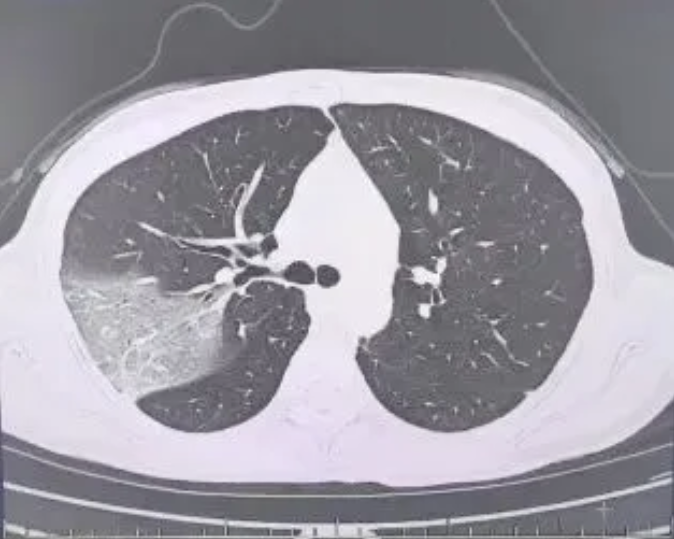

结果情况反而进一步加重:好几叶肺都出现了“白肺”现象,指间血氧饱和度只有88%,血心肌酶谱、肌钙蛋白的指标、肝功能的指标也出现了明显的异常。